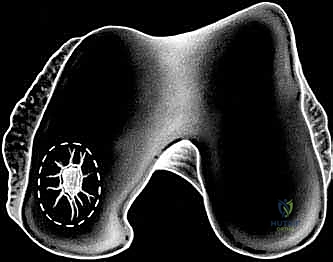

Articular cartilage is unfortunately susceptible to traumatic injuries, leading to partial- or full-thickness chondral or osteochondral defects. Pathologic conditions like osteochondritis dissecans (OCD) or local osteonecrosis also contribute. The critical issue is the cartilage's limited, or often absent, capacity for intrinsic repair due to its avascular nature.

- Partial-thickness lesions: These have a very poor healing potential. Without access to the subchondral blood supply, an inflammatory response cannot be mounted, leaving a persistent defect.

- Full-thickness lesions: While these penetrate the subchondral plate, allowing progenitor cells from the bone marrow to migrate, the repair tissue is typically fibrocartilage. This fibrocartilage, though an attempt at healing, lacks the resilient mechanical properties of native hyaline cartilage and is prone to premature degeneration, delamination, and eventual joint destruction.